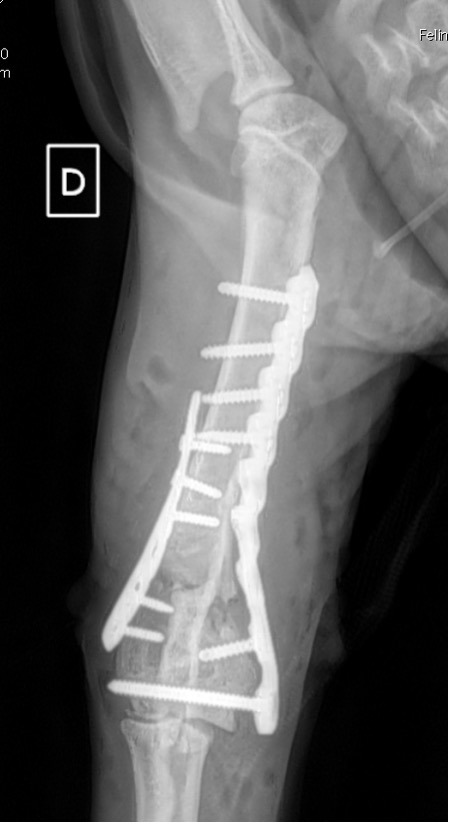

Exemple 3 :

Figure 9 : Pré-Op

Figure 10 : Opération

Figure 11 : Post-Op Immédiat

Figure 12 : Post-Op 1 mois

L’avènement récent des plaques anatomiques constitue une nouvelle option dans le traitement de ces fractures : dans l’exemple 3 (chat Ragdoll), une plaque anatomique médiale de 2 mm acceptant des vis de 1,6 et 2 mm a été utilisée seule avec succès.